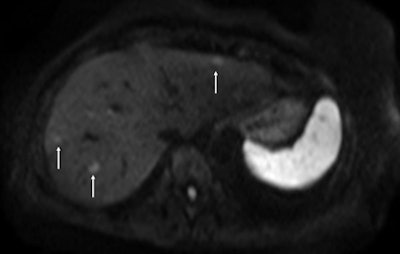

On the diffusion-weighted image, the same lesion is seen as well as two additional metastases: one in the right liver and one in the left liver. All metastases are strongly hyperintense compared to the background liver at b = 600 sec/mm2, indicating restricted diffusion. All of these lesions were surgically confirmed as metastases.Future trends in intra-arterial therapy of liver malignancies were outlined by Dr. Thierry de Baere, from the department of interventional radiology at the IGR. In the intra-arterial treatment of hepatocellular carcinoma, 3D angiography guidance with computer image analysis can improve outcomes of chemoembolization by better depicting liver tumors. Tumor feeding vessels can be depicted with a sensitivity of 93%, with the main limitation being in vessels smaller than 1 mm or when patients have been treated already, he explained.

Fat-suppressed T2-weighted fast spin-echo MR image obtained in 61-year-old man with liver metastases from colorectal cancer. Only one metastasis in the right liver lobe is seen on this slice (arrow). Moreover, this lesion is barely seen because it is located next to a vessel. Images courtesy of Dr. Valerie Vilgrain.